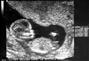

الشهر الخامس .. ماذا يحدث لجنينك؟!

إنه شهر النشاط و السرعه! حيث يحرك الجنين ذراعيه ورجليه بنشاط،وستبدأ الأم بالشعور بحركته بشكلٍ واضح،حيث من الممكن أن ترى حركاته على بطنها، كما يأخذ شكل وجهه شكل وجه الإنسان الطبيعي، وستظهر حواجبه، لكن ستبقى أجفانه مغلقة.في هذه المرحلة، يبلغ طول طفلك 13 سنتيمتراً من رأسه إلى أخمص قدميه ويزن حوالي 140 غراماً،ويبدو هيكله العظمي كالغضروف المطاطي وسرعان ما يصبح أكثر متانة. تبدأ مادة وقائية تسمى “الميلين” (مادة بيضاء دهنية تتكوّن بشكل رئيسي من الدهنيات والبروتين وتغلّف المحور العصبي والأنسجة العصبية، كما تسمى النخاع العظمي النقي) بالالتفاف ببطء حول الحبل النخاعي.سيكتمل نمو المرارة،وتبدأ بإفراز المادة الصفراء التي تساعد على الهضم،كما ستقترب الأسنان اللبنية من اللثة،وسيبدأ الطفل بمص اصبعه في هذا الشهر. من خلال سماعة خاصة، يمكنك الآن سماع نبضات قلب طفلك. لا شيء أكثر إثارة من الإصغاء إلى نبضات قلب طفلك المتسارعة. عندما يداهمك القلق حيال تقدّم حملك، يمكنك التأكد من أن طفلك ينمو بشكل سليم لدى سماع نبضات قلبه. وعندما تشعرين بالضجر وكأن الحمل لن ينتهي أبداً.